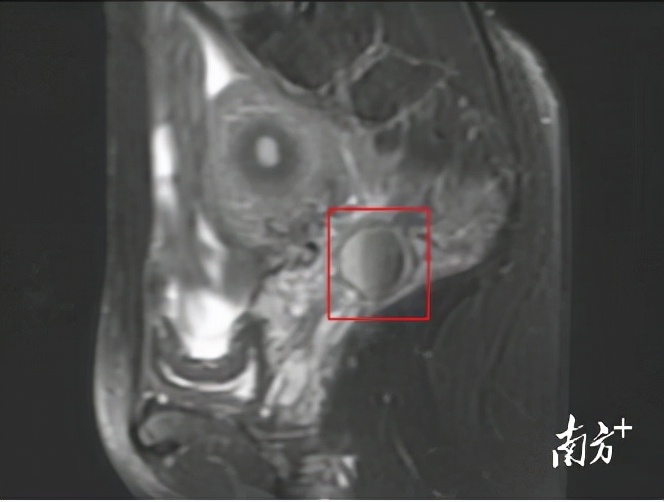

子宫直肠窝囊状异常信号,考虑巧克力囊肿。

“每天大便7、8次,感觉肛门坠胀得厉害,但每次量很少,非常痛……”回忆起就医时的情况,王女士依然后怕。最严重的时候,连小便都很困难,她以为是肠胃出了问题,多次到胃肠外科就诊,但结肠镜、超声肠镜等检查均未见异常。后来,在行下腹部MR检查时,发现“子宫直肠窝数个囊状异常信号,左附件区囊性病变,考虑巧克力囊肿。”

经仔细追问病史,得知王女士有痛经病史3年,且症状逐渐加重。进一步妇检发现其子宫后方、直肠前方可触及大小约6x4x3厘米的实性不规则包块,且向两侧骨盆壁靠近,活动差,触痛;肛查发现距肛门约10厘米处可触及不规则肿物;阴道彩超结果示子宫直肠窝混合回声包块,大小5x2.1厘米。

结合多项检查结果,曾朝阳考虑王女士为“深部浸润型子宫内膜异位症”,也就是发生在盆腔的巧克力囊肿。中医辨证为“气滞血瘀证”。